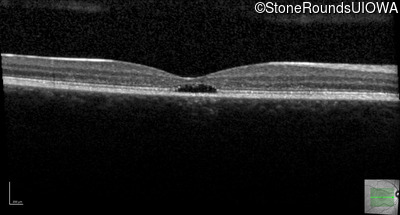

Age at visit: 17 years

OD OS

This 17 year old female first noted problems with her visual acuity around age 13 when she had trouble seeing the projector from the back of the classroom.